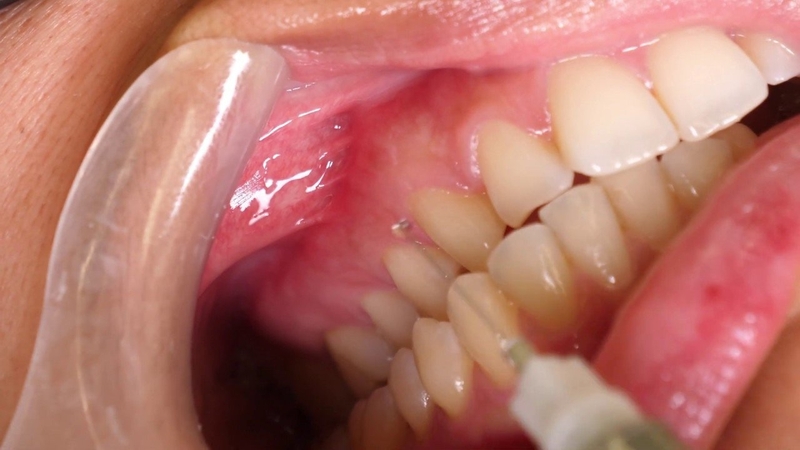

Quy trình tháo mão răng phụ thuộc vào loại mão bạn đang đeo. Với loại mão răng tạm thời, nha sĩ chỉ dùng chất kết dính mềm, dễ dàng có thể tháo ra. Với mão răng vĩnh viễn, việc tháo mão răng cần làm theo đúng quy trình y khoa, đảm bảo an toàn cho người dùng. Quy trình tháo mão răng được thực hiện như sau:

Do mão răng được dùng vật liệu kết dính chặt vào răng đảm bảo không bị rơi ra trong quá trình ăn uống hằng ngày nên việc tháo mão răng sẽ cần tác động một lực khá mạnh. Chính vì vậy, để bạn cảm thấy thoải mái trong khi tháo mão răng, nha sĩ sẽ thực hiện tiêm thuốc tê hoặc bôi, xịt thuốc tê vào vị trí răng cần tháo trước đó. Trong quá trình thực hiện, nha sĩ sẽ làm từ từ và cẩn thận để tránh làm đau bạn.